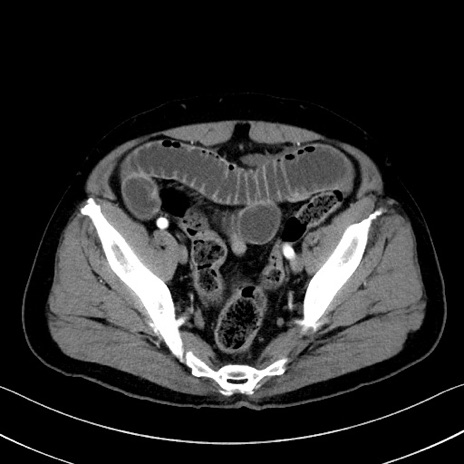

症例35(横断像)

【症例】70歳代 男性

【主訴】腹部膨満、嘔吐

【現病歴】昨日より腹部膨満感出現。本日増悪し、仙痛出現。嘔吐あり、受診。

【既往歴】糖尿病、胆摘後

【身体所見】BP 149/80mmHg、HR 74/min、BT 35.9℃、腹部:膨満、軟、圧痛なし。腸雑音減弱あり。上腹部正中切開瘢痕あり。

【データ】WBC 13500、CRP 1.72